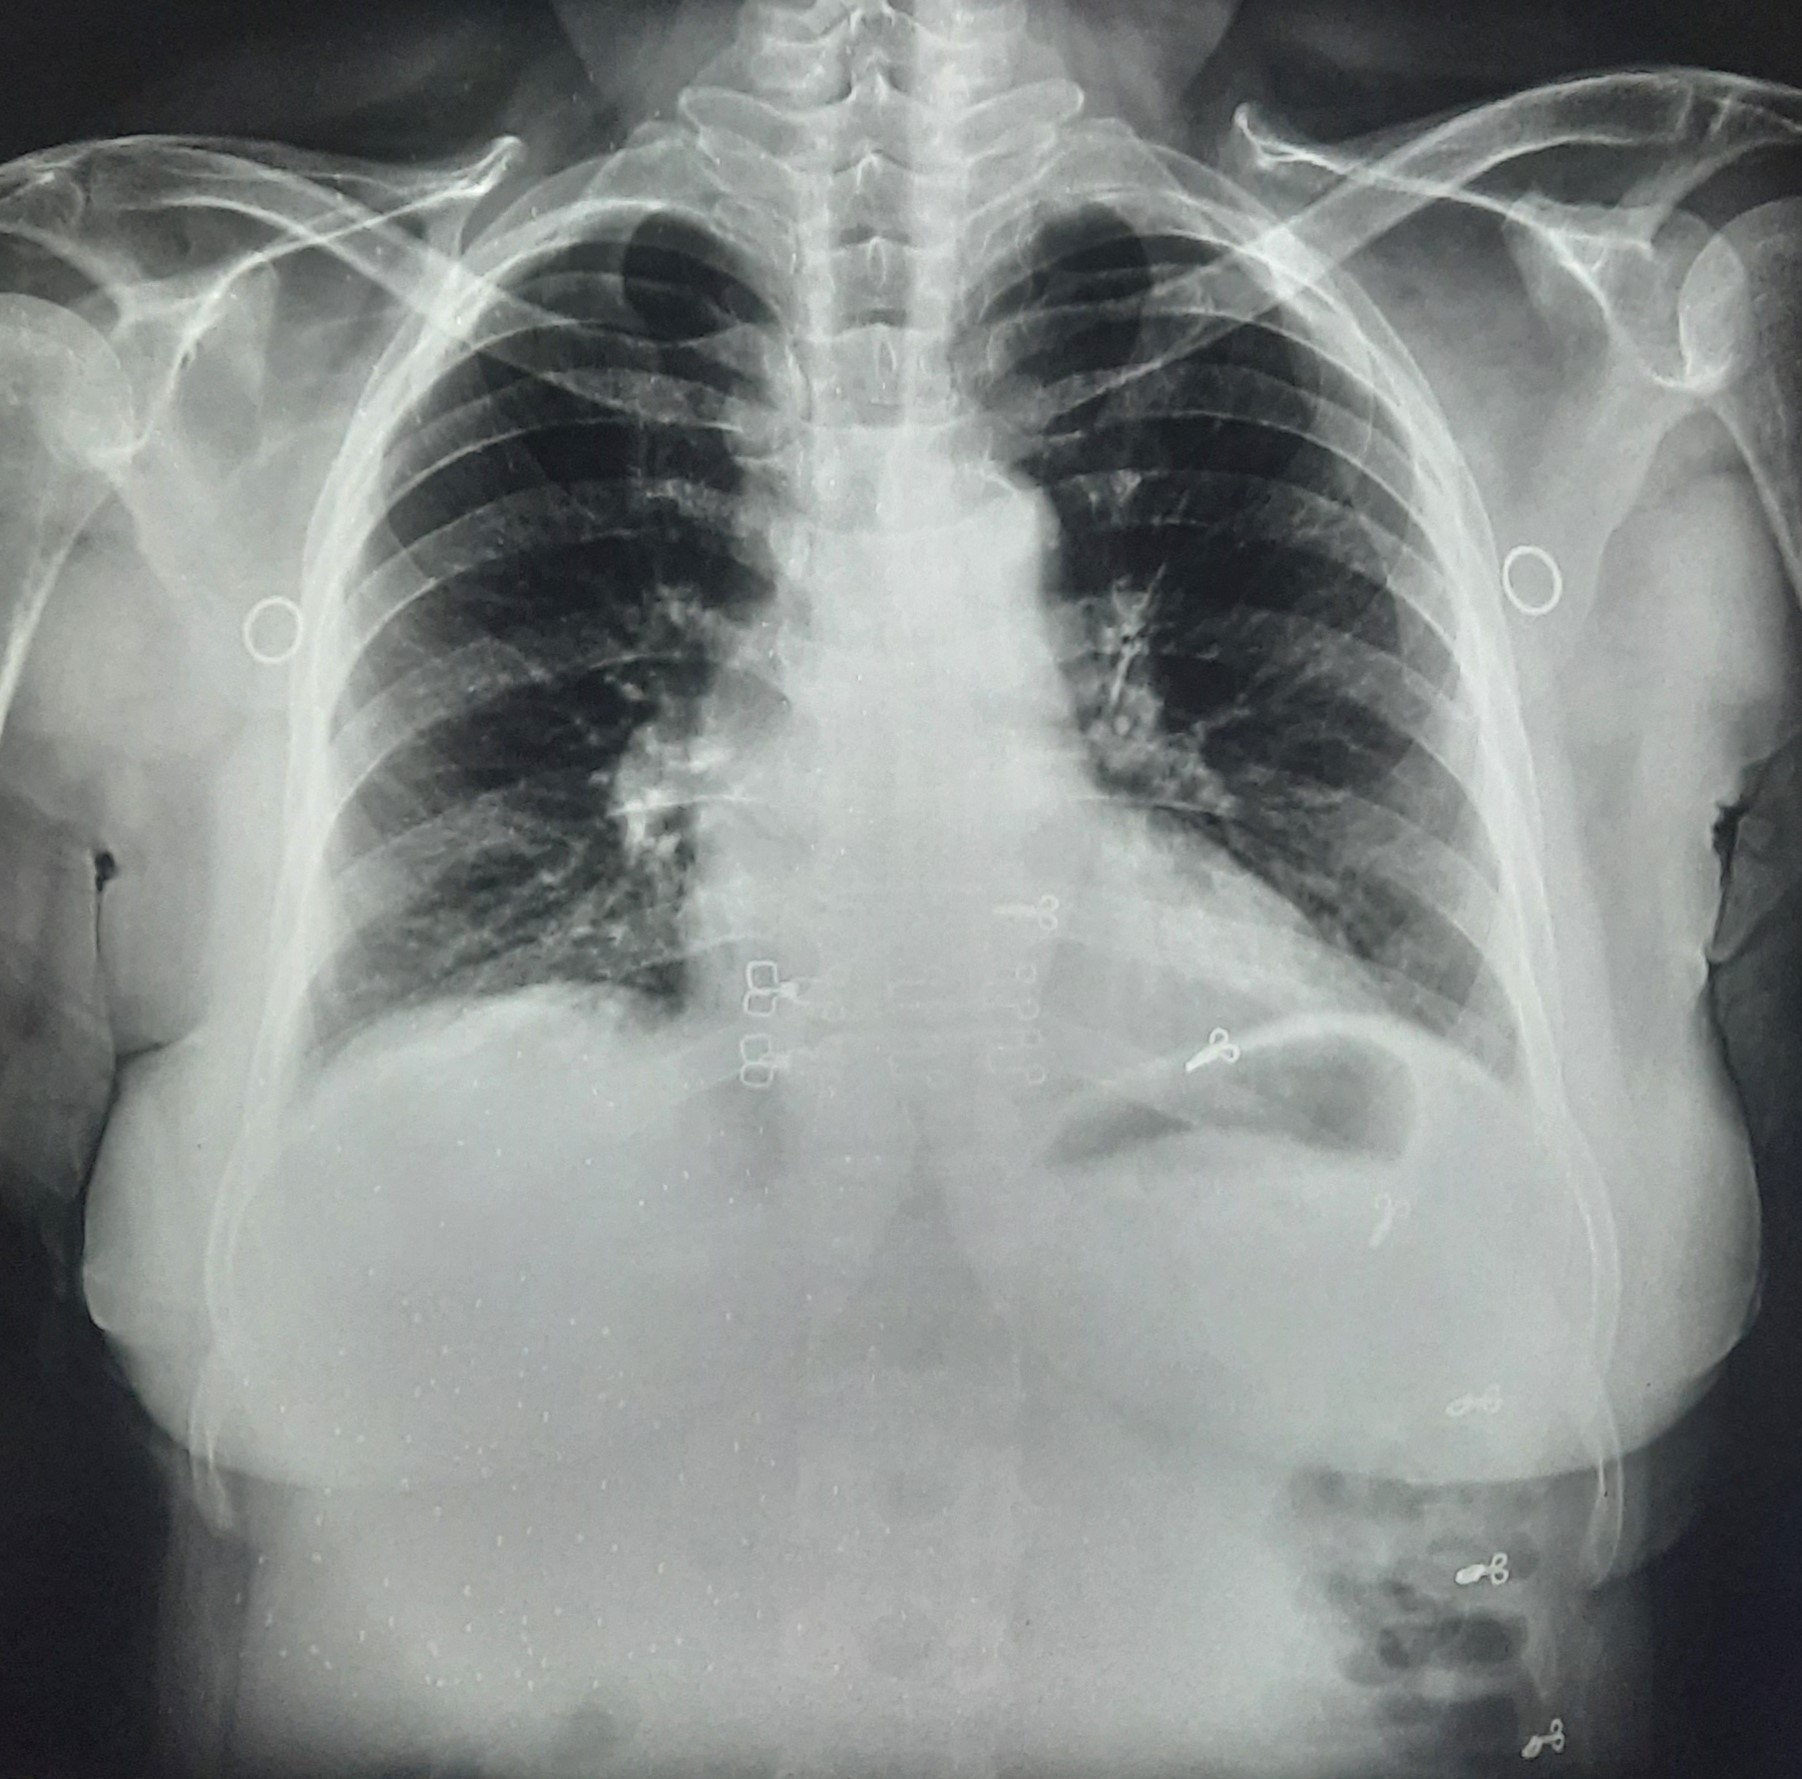

Chest X-Ray Image

IGGMC, Nagpur

29-4164

Hamida Begam